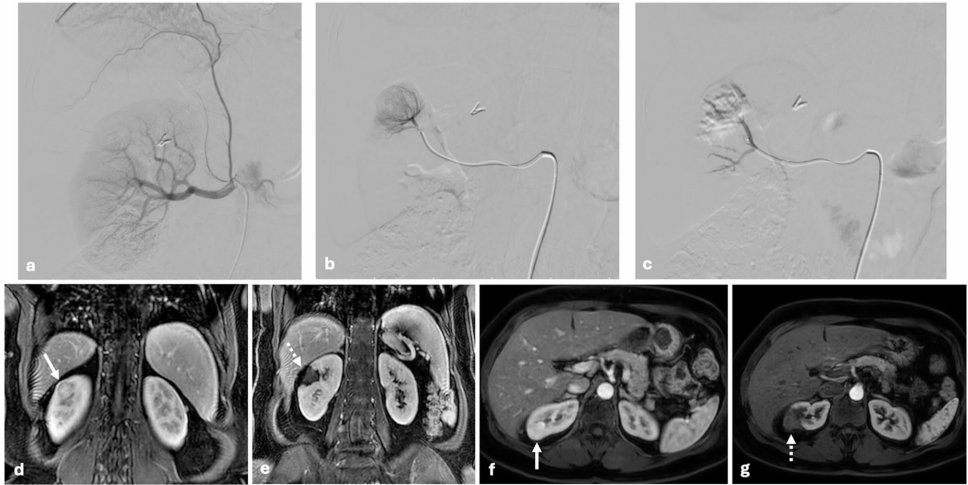

研究采用了多项关键技术方法:1)基于RENAL评分系统客观评估肿瘤解剖复杂度;2)超声引导下经皮MWA治疗,功率75-150W,时间2-7.5分钟;3)DEB-TACE使用100-300μm载药微球(DC Bead)负载多柔比星;4)术后1、3、6、12个月增强CT/MRI随访评估疗效;5)采用KDIGO标准评估肾功能变化。所有患者均经多学科团队评估,排除既往肾脏手术史者。

"Tumor response and residual enhancement"部分发现,单纯MWA组有2例(14.3%)出现残余强化,均发生在RENAL评分≥8且靠近肾窦的肿瘤;而联合组未观察到残余强化,但差异无统计学意义(p=0.62)。

"Renal function outcomes"是研究的关键发现:联合组术后1月eGFR显著下降(72.3→68.5 mL/min/1.73 m2,p=0.04),而MWA组保持稳定(78.2→77.5,p=0.39)。3个月时,联合组更多患者出现CKD分期进展。